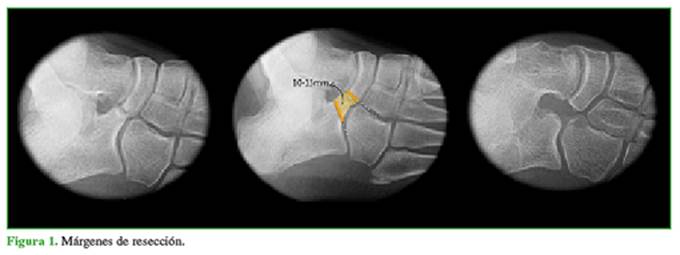

Los resultados funcionales fueron evaluados con la Ankle-Hindfoot Scale de la AOFAS (American Orthopaedics Foot and Ankle Society)11 y la escala analó́gica visual (EAV)12,13 mediante una encuesta telefó́nica. La Ankle-Hindfoot Scale analiza pará́metros subjetivos y objetivos, con valores de 0 a 100 puntos, considerando resultados ó́ptimos directamente proporcionales a la cantidad de puntos. La EAV es una herramienta de medida unidimensional de cá́lculo de la intensidad del dolor, en la cual la respuesta corresponde a un nivel de concordancia mediante la definició́n de una posició́n en una línea continua comprendida entre dos puntos (de 0 a 10). Se definió́ como recidiva radiográ́fica de la barra cuando el margen de resecció́n intraoperatorio disminuyó́ a menos del 50% en la última radiografía oblicua.7 Se consideró́ que un paciente tenía recidiva sintomá́tica si presentaban las características antes mencionadas, pero con dolor que limitaba sus actividades habituales.

El 87,5% de los pacientes estaba completamente asintomá́tico en el último control. Seis pies (5 pacientes) tenían molestias ocasionales que no interferían con las actividades de la vida diaria. Dos pies (4,2%) tenían recidiva radiográ́fica de la coalició́n (Figura 3). Uno de estos pacientes presentó́ dolor, por lo que fue tratado con rehabilitació́n y se logró́ mejorar los síntomas. Ninguno de los dos pacientes requirió́ cirugía de revisió́n.